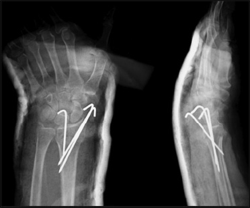

ճաճանչոսկրի դիստալ մետաէպիֆիզի տեղաշարժված կոտրվածք

Կոնտրոլ` համադրումից հետո

Երկրորդային տեղաշարժ 7-10 օր անց